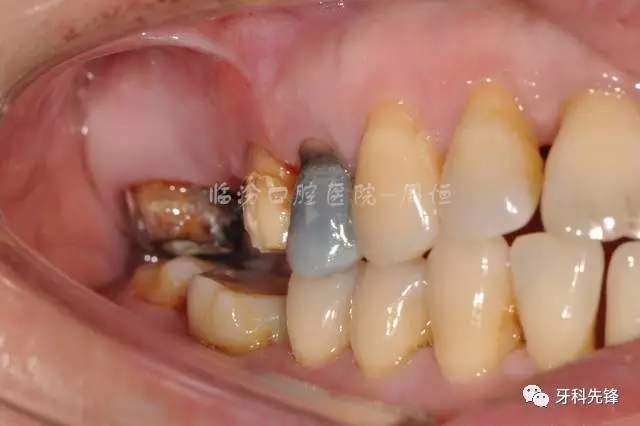

圖4 拆除原修復體牙列照

640.webp (5).jpg